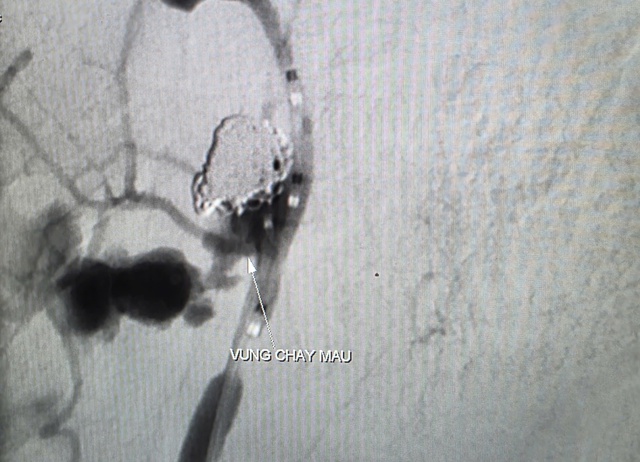

Hình ảnh chụp CT Scan ghi nhận bệnh nhân có ổ giả phình động mạch cảnh trong phải đoạn cổ, dưới nền sọ, cổ túi phình rộng và đang chảy máu

Trước nguy cơ bệnh nhân mất máu ồ ạt, các bác sĩ quyết định thực hiện chụp và can thiệp cầm máu dưới mạch số hóa xóa nền (DSA). Kết quả ghi nhận ổ giả phình động mạch cảnh trong phải đoạn cổ, dưới nền sọ, kích thước 4,2 x 4,8 mm, cổ túi phình rộng và đang chảy máu.